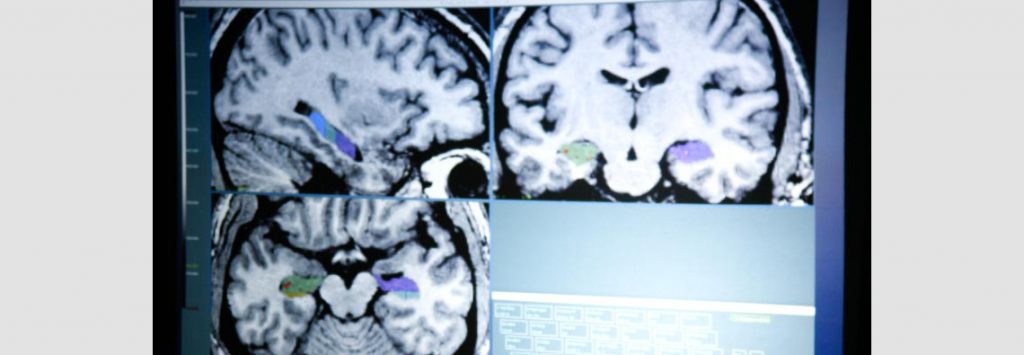

Pendant longtemps, les chercheurs n’avaient que deux façon pour étudier le cerveau. Ils pouvaient utiliser des animaux avec un système nerveux relativement simple tel que le lièvre de mer. Ils pouvaient également étudier les personnes ayant subit des lésions au cerveau et présentant des troubles. L’arrivé de l’IRM fonctionnelle a permis aux chercheurs d’étudier des cerveaux sains en pleine action. Mais la grande plasticité cérébrale limite la compréhension de tous les mécanismes de la mémoire. D’autant plus que les informations importantes stockées dans la mémoire reposent sur différentes parties du cerveau et de façons redondantes.

La mémorisation de ces réseaux pour utilisation à long terme, se passe également durant le sommeil. L’hippocampe et le corps amygdaloïde vont permettre de réactiver les neurones impliqués dans un souvenir pendant plusieurs semaines. Encore une fois cette répétition (virtuelle) va permettre le passage de la mémoire à court terme à celle à long terme.